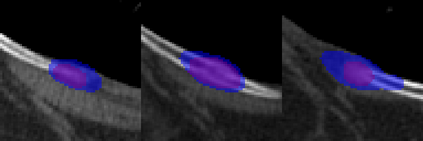

Rib fractures are a common and potentially severe injury that can be challenging and labor-intensive to detect in CT scans. While there have been efforts to address this field, the lack of large-scale annotated datasets and evaluation benchmarks has hindered the development and validation of deep learning algorithms. To address this issue, the RibFrac Challenge was introduced, providing a benchmark dataset of over 5,000 rib fractures from 660 CT scans, with voxel-level instance mask annotations and diagnosis labels for four clinical categories (buckle, nondisplaced, displaced, or segmental). The challenge includes two tracks: a detection (instance segmentation) track evaluated by an FROC-style metric and a classification track evaluated by an F1-style metric. During the MICCAI 2020 challenge period, 243 results were evaluated, and seven teams were invited to participate in the challenge summary. The analysis revealed that several top rib fracture detection solutions achieved performance comparable or even better than human experts. Nevertheless, the current rib fracture classification solutions are hardly clinically applicable, which can be an interesting area in the future. As an active benchmark and research resource, the data and online evaluation of the RibFrac Challenge are available at the challenge website. As an independent contribution, we have also extended our previous internal baseline by incorporating recent advancements in large-scale pretrained networks and point-based rib segmentation techniques. The resulting FracNet+ demonstrates competitive performance in rib fracture detection, which lays a foundation for further research and development in AI-assisted rib fracture detection and diagnosis.